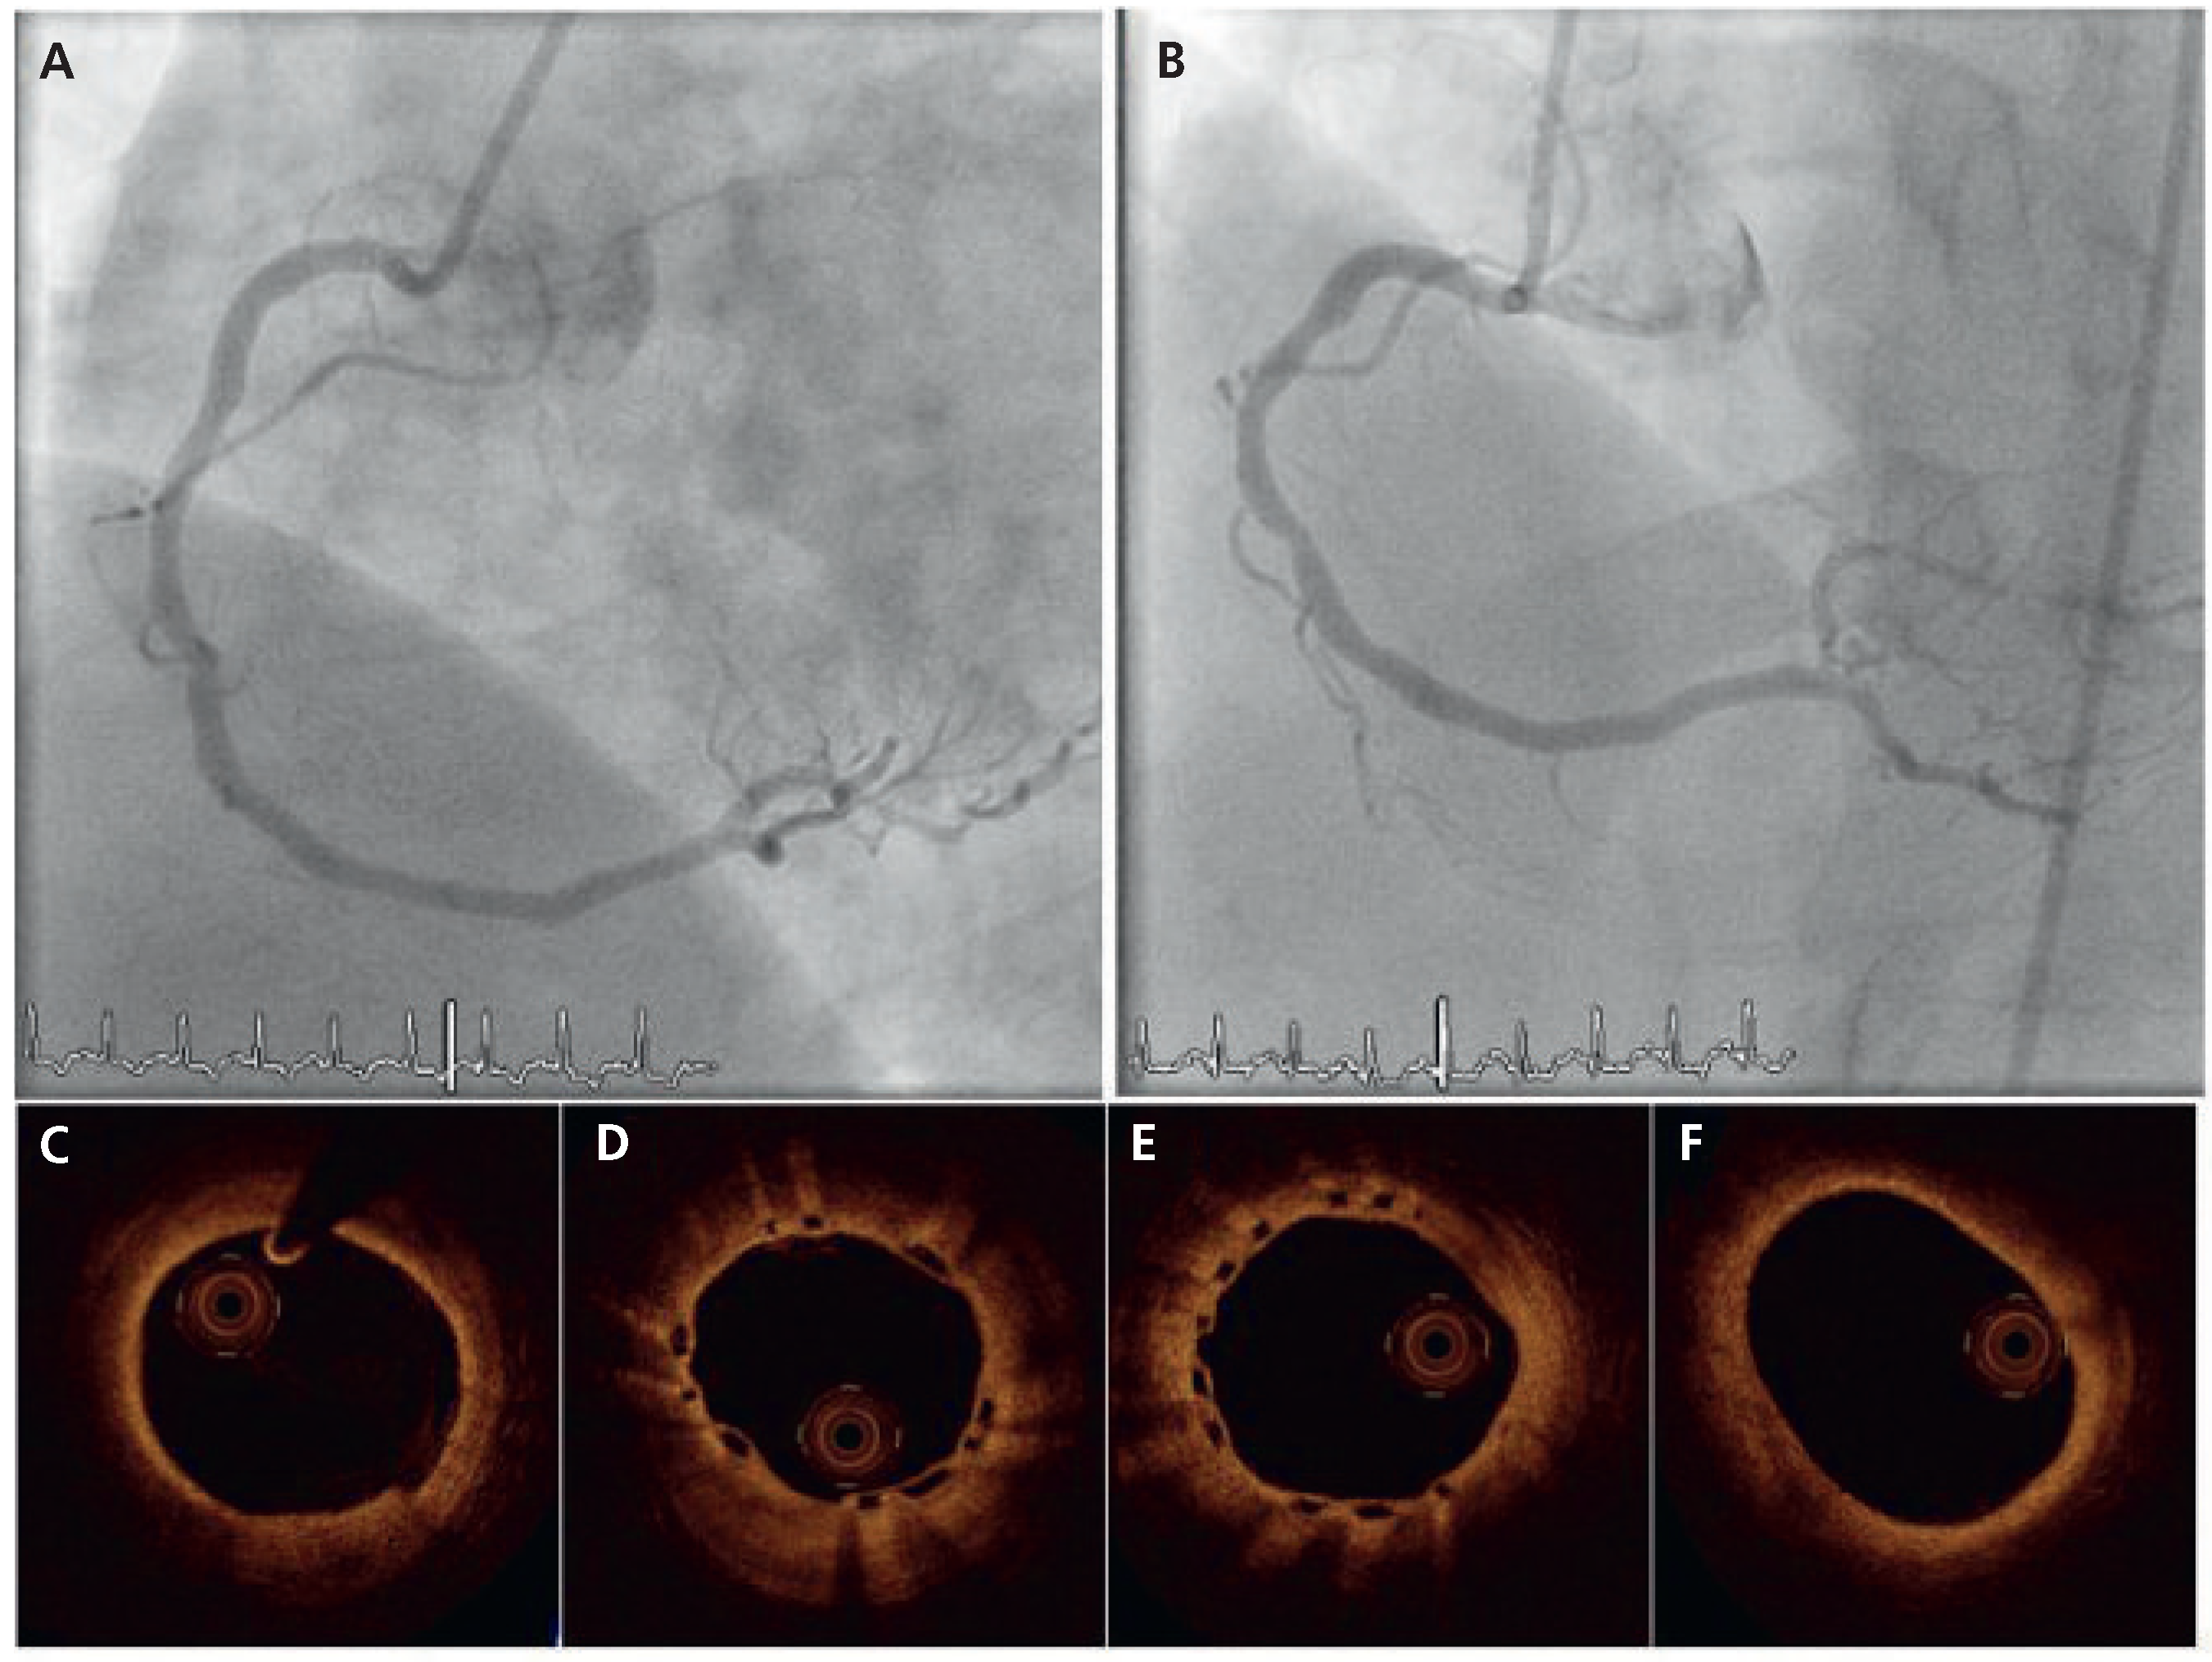

A 51-year-old male was referred for coronary angiography. His known cardiovascular risk factors were insulin-dependent diabetes mellitus, dyslipidaemia, arterial hypertension, obesity (BMI 33 kg/m2) and a family history of coronary artery disease. Coronary angiography (Figure 1) showed patent left main (LM), left anterior descending artery (LAD) and circumflex artery (LCx) without obstructive disease. A second obtuse marginal branch (OM2) and the distal right coronary artery (RCA) demonstrated high-grade stenoses. After angioplasty of OM2 with subsequent implantation of one 2.25 × 12 mm-everolimus-eluting stent, (XIENCE V, Abbott Vascular, Santa Clara, CA), at 16 atm, the stenosis in the RCA was treated with a bio-resorbable everolimus-eluting coronary scaffold. Briefly, a 6F Judkins right 4 guiding catheter was positioned at the RCA ostium. A 0.014’’ guidewire (BMW, Abbott Vascular, Santa Clara, CA) was advanced into the posterolateral branch and the lesion was treated by single balloon inflation (3.0 × 12 mm-Apex, Boston Scientific, Nantik, MA), at 12 atm, which was followed by the implantation of one 3.0 × 18 mm-everolimus-eluting bioresorbable vascular scaffold, (BVS, Abbott Vascular, Santa Clara, CA), at 12 atm. The control angiography, the intravascular ultrasound and the optical coherence tomography showed satisfactory results. The recovery was uneventful and the patient was discharged on the following day. A lifelong prescription of aspirin (100 mg daily) was prescribed, and clopidogrel (75 mg daily) was prescribed for 12 months. At 6-month follow-up (Figure 2), control angiography was performed and demonstrated a smooth artery without visual angiographic late loss. Both an intravascular ultrasound study and optical coherence tomography revealed neoendothelialisation of the scaffold struts without significant vessel shrinkage or excessive neointimal hyperplasia. Clinical follow-up to 12 months was uncomplicated.

Figure 2.

Angiographic (A,B) and OCT findings (C–F) at 6-month angiographic follow-up.